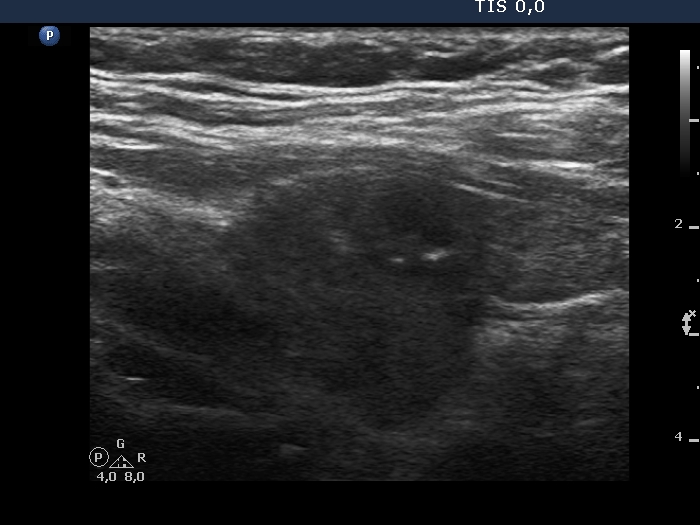

Examination in 2020 (third row of images):

Comment. This story draws attention to how important it may be to be aware of the results of a previous study. By result I do not mean the findings, but the archived recordings.Clinical data: The patient came to a routine follow-up. She had no complaints.

Palpation: Both lobes were a bit firm on palpation. There was a not firm nodule in the right lobe.

Laboratory test: TSH 3.38 mIU/L on daily 125 microgram levothyroxine.

Ultrasonography. The previously cystic lesion has spontaneously decreased in size, the cystic fluid has disappeared. However, the hyperechogenic foci were still visible. If we had only seen this current study, we would have had to regard these echogenic granules microcalcifications.

We recommended that she takes the replacement therapy at the same dose and has a TSH scan after a year and an ultrasound scan after three years.